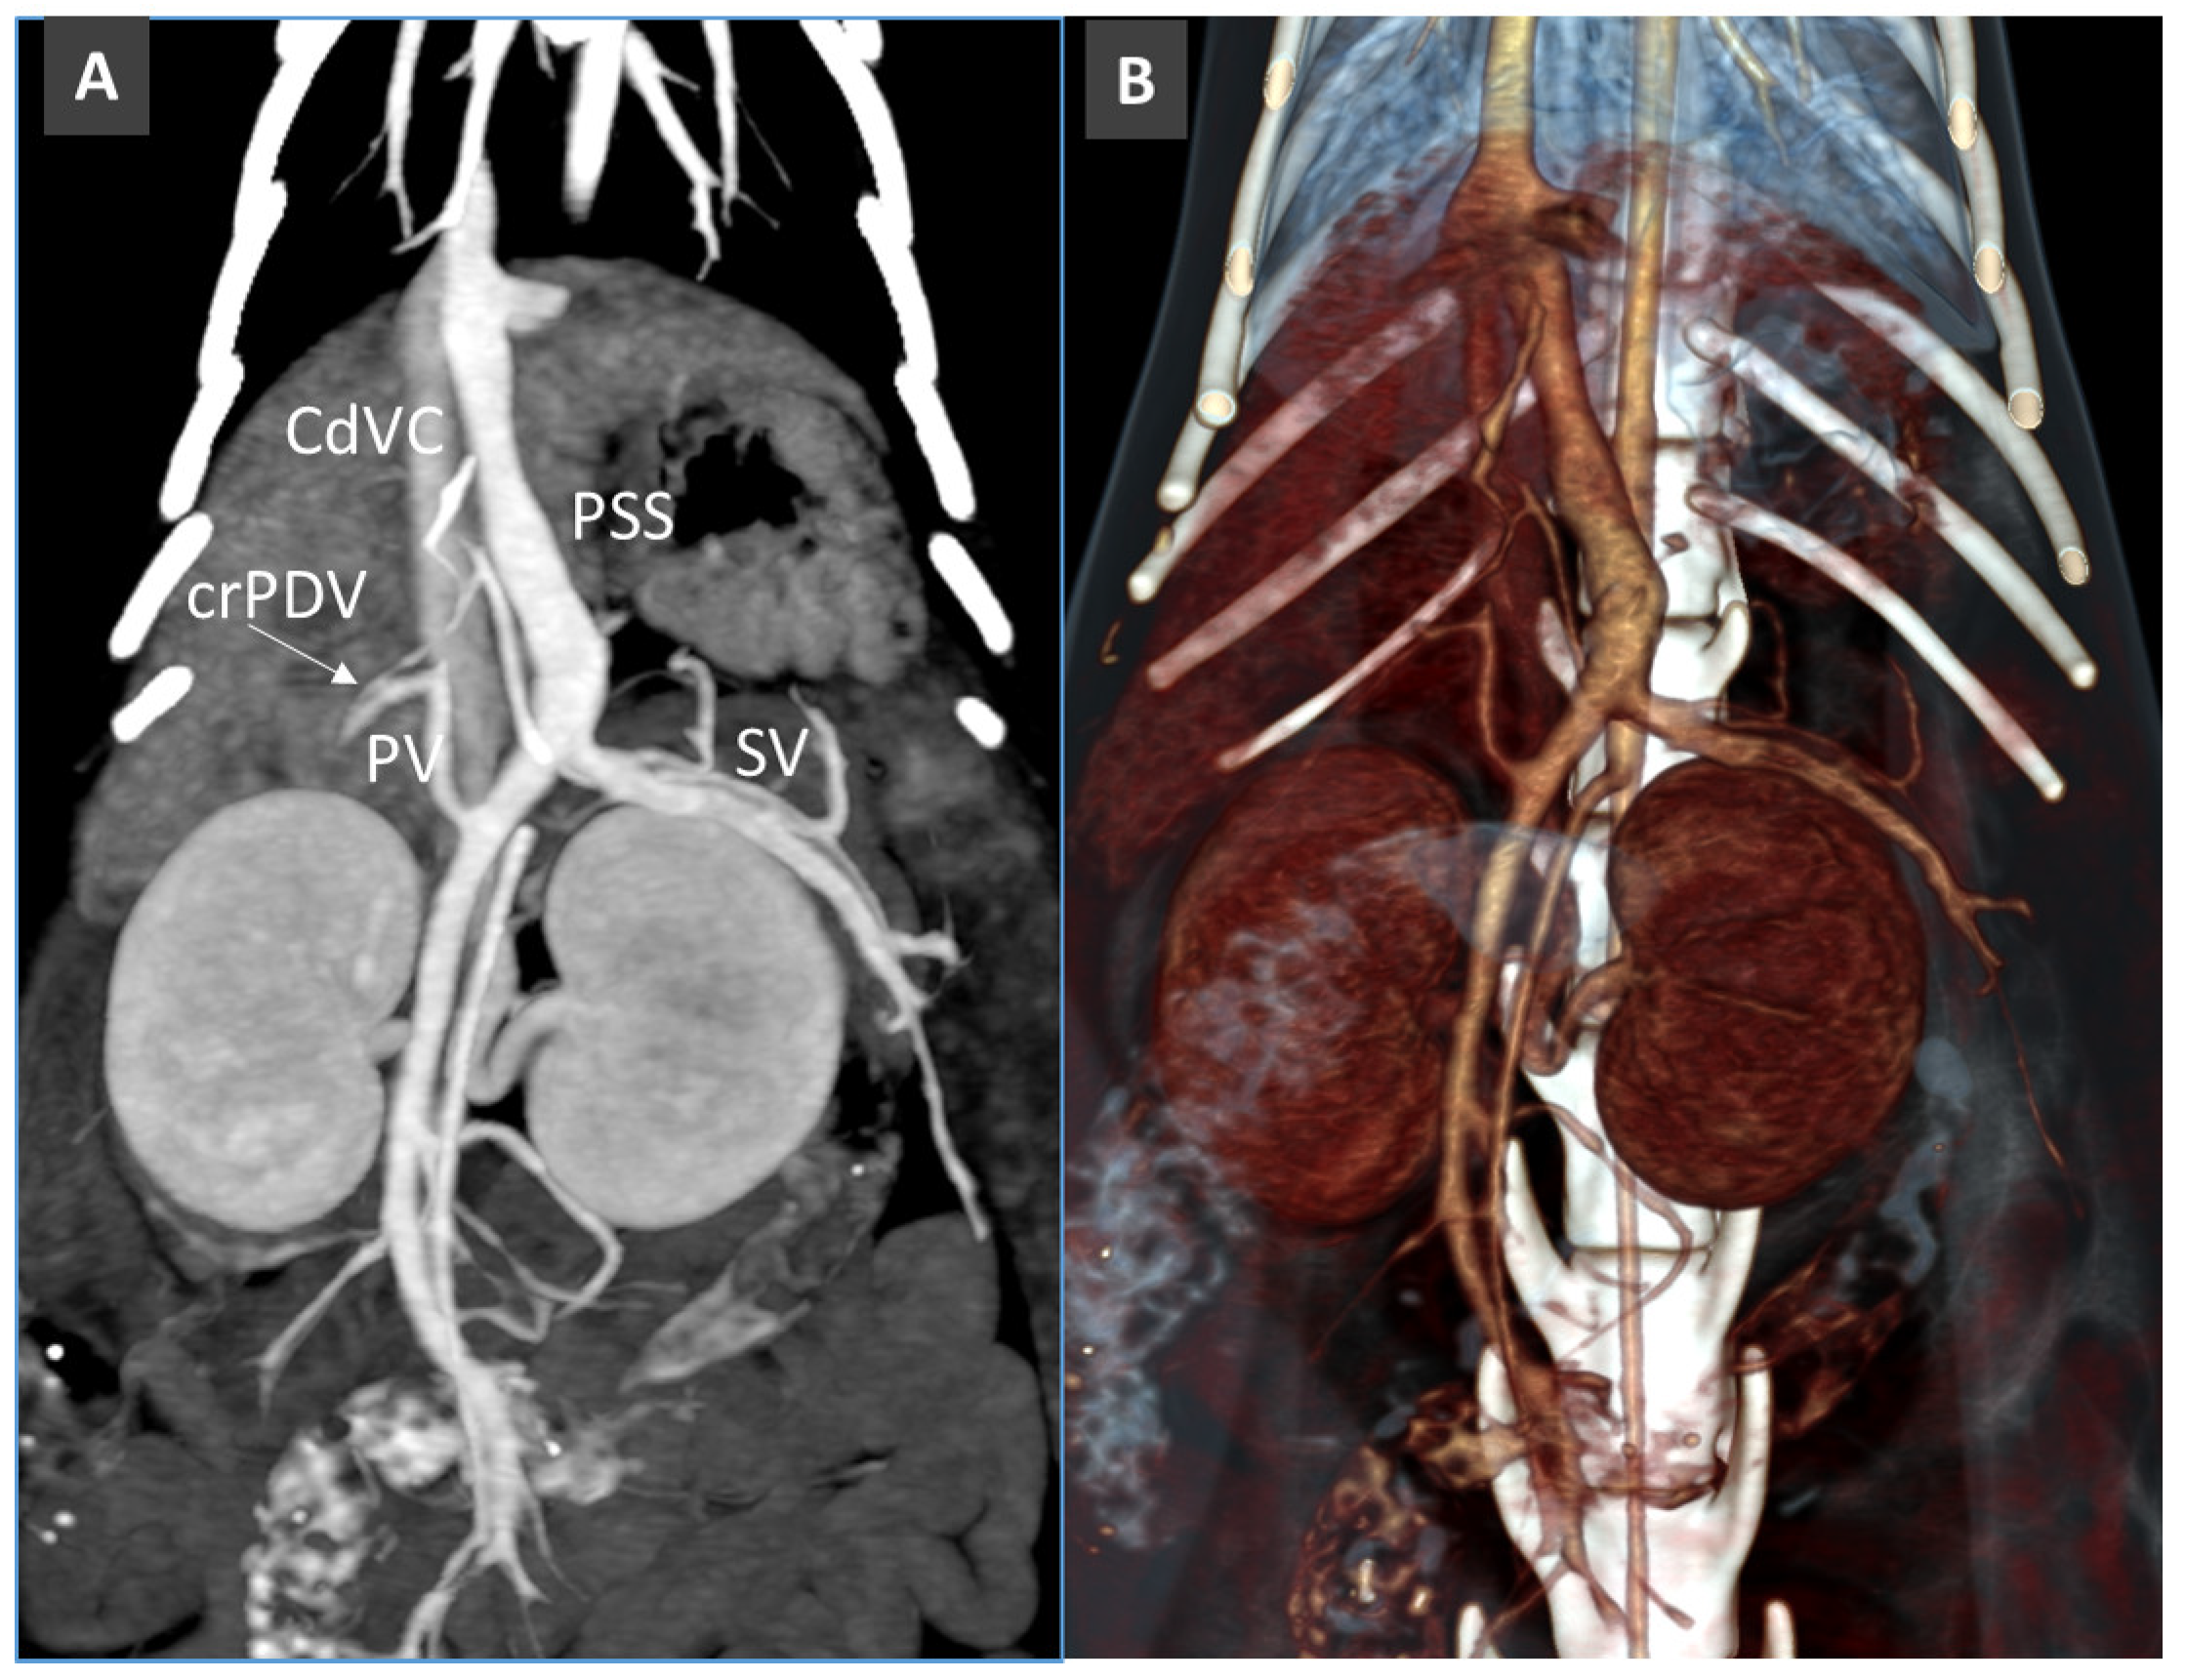

Congenital Portosystemic Shunt

3.8. Porto-Portal Collaterals or Cavernous Transformation of the Portal Vein